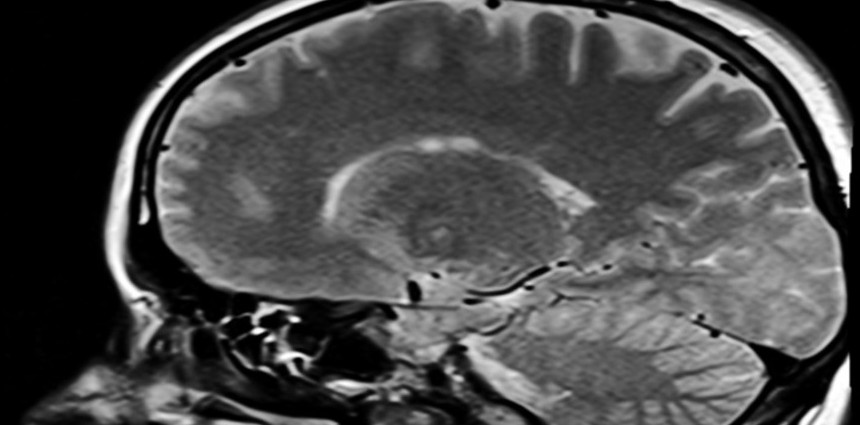

США — не единственная страна, ведущая разработки мозговых имплантов, позволяющих людям с параличом конечностей управлять компьютером буквально при помощи мысли. Наибольшую известность в этой сфере получил стартап Neuralink Илона Маска (Elon Musk), однако недавно Китай также успешно провёл клинические испытания по вживлению нейроимпланта в мозг человека.

Об этом со ссылкой на Global Times сообщает Bloomberg, отмечая, что КНР становится второй страной в мире, добившейся успехов на данном направлении. Пациент с параличом четырёх конечностей, как отмечается,

перенёс операцию по вживлению импланта в головной мозг в марте этого года. К настоящему времени он освоил управление курсором мыши в компьютерных играх, включая гоночные симуляторы и шахматы. Операция была проведена специалистами Шанхайского исследовательского центра, который изучает проблемы головного мозга.

Китайские источники также утверждают, что созданный в Поднебесной мозговой имплант на данный момент является самым компактным в мире, имея диаметр 26 мм и толщину корпуса 6 мм. По оценкам китайских специалистов, в своём применении такой имплант обеспечивает в 100 раз больше гибкости по сравнению с решением Neuralink. На следующем этапе китайские учёные намереваются научить пациента управлять роботизированным манипулятором при помощи силы мысли: захватывать предметы и удерживать чашку с напитком. Если всё пойдёт по плану, то данный мозговой имплант получит одобрение от китайских регуляторов, и выйдет на рынок ориентировочно в 2028 году.